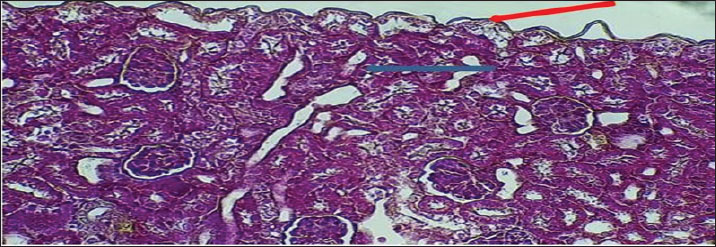

The fundamental unit of kidney structure and function presented in the Introduction was the nephron, which was a combination of the glomerulus, proximal convoluted tubule, loop of Henle, distal convoluted tubule, and collecting duct. When stained with hematoxylin and eosin, the low-power study of Fig. 1 marks off two regions in the kidney: the cortex on the outside and the medulla on the inside. The thin connective tissue capsule encompasses the cortical area on the outside of the structure (at the blue arrow). The renal cortex holds renal corpuscles and some tubules, but the interior appears mostly tubular because it consists of Henle collecting ducts and loops. One can observe renal corpuscles, which are marked by visible Bowman’s capsules, as indicated by a yellow arrow. In Figure 2, Alcian blue staining shows the renal cortex in the 40x section and proximal and distal convoluted tubules. The simple cuboidal epithelium (indicated by red arrows) on the tubules is a special feature of early postnatal development. Near the corpuscle, glomerular arterioles (blue arrows) grow to aid blood circulation. Using the Alcian stain, glycosaminoglycans located in basement membranes and the extracellular matrix are visualized, and this helps make epithelial cells more noticeable. In Figure 3, the Masson’s Trichrome-stained picture at 10x showed how the kidney’s connective tissue is organized. A thin layer (marked with the red arrow) made of fibers surrounds the organ, giving the tissue a blue-green color because of the collagen. In Figure 4, the section from the 1-week shows images of both H&E staining and Alcian blue staining of the ureter cross-sections. The ureteral lumen is small throughout and runs in the center (pictured by the red arrow). On the inside, there was a small layer of squamous epithelial cells (yellow arrows) and a thin layer of muscle envelope (blue arrows) essential for making urine flow. Alcian blue mucopolysaccharides were found in the epithelium and the space below, suggesting that the mucosa was developing at the beginning of the week. In Figure 5, two 40x showed the ureter stained with PAS and Masson’s Trichrome. The yellow arrow shows the epithelial layer, the blue arrows show circular smooth muscle fibers, and the red arrow shows the longitudinal muscle layer. The outer layer is indicated by the black arrow. The Masson stain in panel B highlights the shape and layers of the smooth muscle, where collagen fibers are shown in blue and muscle cells are shown in red to clearly display the early development of the ureter.

Fig. 1. Cross-histological section of kidneys from 1-week-old hamsters from two distinct areas: the outer cortex with a thin capsule and the inner medulla. Note renal), renal corpuscles with a thin Bowman capsule. 10x. H&E stain.

Fig. 2. Cross-histological section of cortex of 1-week-old hamsters showing the proximal and distal tubules with simple cuboidal epithelium (red arrow) and glomerulus arterioles (blue arrow). 40x. Alcian blue staining.

Fig. 3. Cross-histological section of cortex of 1-week-old hamsters showing the proximal and distal tubules with simple cuboidal epithelium (red arrow) and glomerulus arterioles (blue arrow). 40x. Alcian blue staining.

At 1 week of age, the kidney of the hamster showed typical signs of early postnatal development, such as a defined renal capsule, not so mature renal corpuscles with narrow spaces where blood fluid was processed, and the inner tubule walls were mainly made up of simple cuboidal cells. These results showed that in rodents, development of the kidney glomerular and tubular structure continues shortly after birth, serving the kidney’s maturation (Kose et al., 2020). Indeed, the thin connective capsule seen on both H&E and Masson’s Trichrome stain indicates that mesenchymal cells are already dense, and this observation fits with what has been found in developing rodent species, where the renal capsule becomes thicker and starts changing by the second week after birth (Singh et al., 2022). A hamster kidney has renal corpuscles with a narrow space for forming urine, and the Bowman’s capsule is less developed, indicating that glomerular growth in the hamster has just begun. These observations are consistent with previous findings on neonatal rats and mice that the kidneys’ filtration ability was limited during the first week of life (Lee et al., 2019). Observing articular arteries near the glomeruli is essential because it represents vascular recruitment that supports the continuous creation of blood vessels in the developing kidney tissue (Chou et al., 2021). In addition, Alcian blue staining confirmed the presence of acidic glycosaminoglycans in the basement membranes, which is an important early indicator of nephron development and the formation of tubule centers in epithelial cells (Sajjad et al., 2020). The appearance of Henle’s loops and collecting ducts on slides with PAS and Van Gieson stains shows that urine was being concentrated at this point, albeit only to a small extent in the renal medulla. As Zhang et al. (2023) described in their study, the simple squamous epithelium found in the thin limbs of Henle’s loop in neonatal rodents was a sign that the structure was immature and unsuitable for effective countercurrent exchange until the third postnatal week. In addition, the PAS stain revealed cells that looked like zymogens, which might match immature tubular epithelial cells that were not yet fully differentiated (El-Mahdy et al., 2019). Postnatal growth and development in the ureter were observed after H&E, Alcian blue, PAS, and Masson’s trichrome staining. The fact that the lumen was narrow and surrounded by a simple squamous epithelium, along with the emergence of a double layer of smooth muscle tissue, suggests the initiation of peristalsis. In newborn rats, smooth muscle development occurs in the late fetal stage and continues after birth to form the two muscle layers (Matsumoto et al., 2020). At this point, Alcian blue detected in the ureter confirms the presence of mucopolysaccharides that could help protect the lumen and make the tract more flexible (Ishak et al., 2022). It could also show early formation of the stromal matrix in the capsule and interstitium by finding collagen fibers during Masson’s trichrome staining. It is essential to keep the structure of the kidneys intact and to attach the nephrons. Wu et al. (2021) revealed a similar behavior in the kidneys of newborns, as increased collagen types I and III are seen during the first postnatal week, and these help form tubules and stabilize blood vessels. At 1 week of age, the hamster kidney and ureter are changing from a prenatal structure to a fully functioning one. They confirm what has been found in mice and improve the development of the kidneys and ureters in hamsters, a major animal used in renal medical studies (Al-Rubaye et al., 2018; Kim et al., 2024). The 2-week observations revealed that both glomeruli and tubules were maturing and specializing in the kidney. The cortex appears thicker, has more cells, and the parenchyma is organized more clearly in these structures. Bowman’s capsules were thicker, and the renal corpuscles were also more formed. Important changes in the kidney, including elongation of podocyte foot processes and growth of glomerular capillaries, occur between days 10 and 15 after birth (Abdel-Rahman et al., 2020). The presence of PAS-positive material in the capsule and basement membranes of Bowman’s capsule is another indication of glycoprotein accumulation during postnatal kidney development. The renal corpuscles stand out with their unique build and know-how of filtering blood. A further examination in neonatal Wistar rats indicated that the parietal epithelial cells depositing more extracellular matrix material caused the thickening of the Bowman’s capsule during the second week postbirth (Salem et al., 2021). Zymogen-like cells in the proximal tubular epithelium might start the development of enzyme creation, as it was shown in rabbit and guinea pig kidneys when renal tubules are starting to differentiate (Zahra et al., 2019). The medullary region contains vertically arranged, straight tubules that are covered by simple columnar epithelium. They probably represent the early part of the collecting ducts and the thick parts of the ascending limbs. Setting up the renal structure in this manner was necessary to develop the main renal countercurrent system. These developments in medullary extensions and epithelium were in line with the explanations provided by Balasubramanian et al. (2018), who said that they boost both sodium reabsorption and urine concentration in rats beginning on day 14 after birth. In this process, the Van Gieson stain enables the maturation of the renal tissue and supports the correct placement and stability of nephrons. There were more layers in the renal capsule, indicating the readiness of the tissue to handle the increased blood pressure in the artery. In Syrian hamsters and tree shrews, the renal capsule thickens with fibroblasts and collagen I during early growth, acting as added protection from trauma (Nasr et al., 2023). The better organization of subcapsular nephrons indicates that nephrogenesis is very close to finishing—a stage usually completed at the end of the second week in most rodent models (Barakat et al., 2019). When viewed under Alcian blue staining, the transition zone of the ureter has several cell layers and exhibits heavy accumulation of mucus. The muscularis muscle layer develops into circular and longitudinal bundles to allow regular urine movements. A study on mouse postnatal ureter development found that muscle cells begin to contract with coordination once the tube’s layer and inner lining have been completed on Days 10–18 (Farag et al., 2022). The widening of the ureter’s lumen, which was observed in slices stained with hematoxylin and eosin and with PAS, also demonstrates the organ’s readiness for more renal urine. These results indicate that on postnatal day 14, there were significant changes in the glomerular, tubular, capsular, and ureteral structures of the kidney and ureter. As a result, these changes ensure that vital filtering, reabsorption, and elimination functions are available for self-control of the body, as backed up by studies of several rodents and ensuing histological and ultrastructural sessions (Al-Khafaji et al., 2020; Alshammari et al., 2023). When the Alcian blue stain was positive, mucopolysaccharides were still being produced for the protection of the urothelium, and when PAS staining was present, it indicated that the basement membrane had grown and differentiated properly. In hamsters, the kidneys show significant improvement at 3 weeks after birth as the renal corpuscles, proximal tubules, and blood vessels can be easily distinguished. Mature glomerular tufts and an increase in the size of Bowman’s spaces which was clearly observed by Masson’s trichrome dye staining. Similar to 17- to 21-day-old mice and Mongolian gerbils, this same order of development is typical for nephron maturity and glomerular capillaries in rats (Al-Dosari et al., 2021). Clear brush borders in the proximal convoluted tubules show that the kidneys have achieved a significant absorptive function, reflecting the situation in rodent models (Saleh et al., 2023). PAS-stained cortex reveals that the capsule and widespread tubules are clearly visible. This suggests that the blood vessels were being organized and the tubular alignment was increasing. In the striated distal segments, the PAS-positive reaction indicates that more basement membrane proteins were present, which enhanced ion movement and strengthened the tubules while reabsorption was going on (Okasha et al., 2022). Similar to previous research in gerbil and hamster models, the so-called regenerating zone shrinks around the third postnatal week, indicating that nephron growth is finished and the last maturation phase begins (Abbas et al., 2021). The glomerular structure was stained using Van Gieson stain to clearly separate the layers of Bowman’s capsule, visceral, and parietal. Evidence from previous studies was confirmed by the presence of red collagen in the capsular region, indicating that extracellular matrix deposits are important for stabilizing kidney growth after birth (El-Taher and Mahrous, 2020). In addition, the structure of the organized capillary beds and division of glomerular layers corresponds to the time when podocytes and endothelial cells were fully matured in week three (Mekawy et al., 2020). The ureters have a wider, healthier lumen, and their epithelium and muscle layer components were clearly differentiated. The ability to distinguish circular from longitudinal smooth muscle fibers using Masson’s trichrome and Van Gieson staining is important for the development of peristalsis in the intestines. Similar muscle changes peak between days 18 and 24 in the postnatal rats’ ureters, helping them send urine easier (Mohammed et al., 2022). On the histochemical side, the epithelium was seen to store mucopolysaccharides using Alcian blue staining, and the basement membrane was fully developed according to results from PAS staining in the image. At this point, the urothelium showed glycoconjugates because the mucosal barrier was strengthened, a finding that resembles results from a rabbit study where the study saw increased mucin in response to an increasing urine osmolarity (Kamal et al., 2021). Also, the reactivity to PAS confirms that the urothelial cells have stabilized and developed into the right type of cells, just as was observed in other rodent kidney–ureter studies conducted after birth (Shaker et al., 2023). By 3 weeks, the kidney and ureter of the hamster have developed almost fully, as indicated by laboratory findings and what has been observed in other mammals. Such changes were an indicator that the tissue was shifting to performing its basic functions, involving more detailed cell divisions, a rise in blood vessels, and remodeling of the supporting structures (Younis et al., 2022). At 2 months, the nephron structure, found in the renal cortex, was mature and included in each renal corpuscle as well as the proximal and distal tubules. In these pictures, the renal corpuscles appear compact; there is a clear space around the Bowman’s capsule, and the tubules are easily visible. The presence of PAS-positivity in the proximal tubules indicates that the basement membrane is fully mature, has an abundance of glycoproteins, and aids in maintaining the correctness and selectivity of reabsorption (Zhou et al., 2021). It was obvious from the stain that the proximal cells have denser cytoplasm, while the distal ones have widened lumens and mildly stained cytoplasm due to their function in salt and water reabsorption (Chen et al., 2020). The vascular pole contents indicate that the renal corpuscle has grown and is ready to work. The juxtaglomerular apparatus yellow arrows helps regulate the body’s blood pressure and control the rate of filtration through the launch of renin. It has been noted that the morphology of juxtaglomerular cells in rats matures and they can react to major signals in the body by weeks 6–8 (El-Nahas et al., 2019). In addition, both Masson’s and Van Gieson in panels A and B accentuate the clearly defined system of fibers around the glomerular capillaries, which stabilizes the matrix and shows normal endothelial-mesangial relations in older rodents (Ahmed et al., 2021). The ureter had a large lumen, a well-structured epithelium, and smooth muscle groups. Because the eggfish’s structure has a distinct circular layer, a longitudinal layer, and a thick serosa, it can perform complex contractions. This was in line with the observation made by Azzam AM Ismail and Khalil (2022), who said that the ureter was fully developed and starts contracting and moving in waves to help empty the bladder in rats that were no longer nursing. Many layers in the smooth muscle make it possible for the ureter to propel and smoothly modulate fluid. The epithelium has squamous features and keeps its junctions intact, whereas the smooth muscle layers become thicker and are divided into segments. In panel B, green arrowed perivascular adipose tissue was found around the ureter, which enhances this region’s ability to get nutrients and was present in adult mammalian ureters to support their functioning (Talaat et al., 2020). The reactivity with Alcian blue and PAS showed that glycosaminoglycans were being produced continuously, helping the epithelium remain flexible and save the kidneys from exposure to dangerous urinary solutes (Salem et al., 2023). Renal and ureteral changes appear at this age because the organs have finished their development. Lab discoveries in rodents show that the structure and function of the nephron and collecting system resemble those of an adult around 6–8 weeks after birth (Mostafa et al., 2022). This information about the maturation of fast golden hamsters could give more insight into their usefulness in nephron and urological studies. Further elaboration has been given on the significance of glomerular and tubular development maturation. The development of glomeruli is critical for the development of an effective filtration barrier because the formation of podocyte foot processes and capillary loops directly increases glomerular filtration capacity. Likewise, proximal and distal tube maturation is essential for reabsorption and secretion to achieve electrolyte and fluid balance. These structural changes ensure that the kidney functions as a homeostatic organ when it reaches adulthood. The results of the current research correspond with the prior observations in rodents, which revealed that immature glomeruli and undifferentiated tubular epithelium make immature kidneys unable to filter as well (Lee et al., 2019; Kose et al., 2020). Bowman capsule progressive thickening and tubular epithelial differentiation occurred as previously described in rats, hamsters, and gerbils during the second and third postnatal weeks (Abdel-Rahman et al., 2020; Abbas et al., 2021). These comparisons indicate that the structural maturation in golden hamsters is similar to that in other rodent models and that nephron development is important in determining normal renal physiology. Our further work intends to use this study to investigate the molecular pathways in renal and ureteral development with high-order histochemical and immunohistochemical procedures that could give us a deeper insight into this subject pertinent to the fields of veterinary and biomedical sciences.